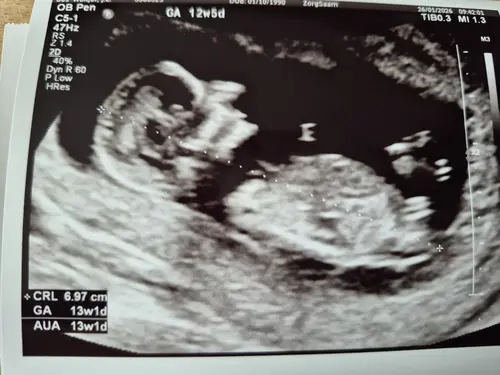

Vandaag 12+5. Ik heb vandaag de 13 weken echo gehad. Ik denk een meisje, wat denken jullie?

Jaaa ik raak zoo zenuwachtig hahaha maar dat heb je met die theorie毛n natuurlijk. Ik zie zelf idd ook meisjes nub

Het geslacht is niet helemaal duidelijk te zien, dus het zou zo goed een meisje als jongen kunnen zijn. Maar ik gok een meisje! 馃

Is dat uitsteeksel dAn niet de nub? Dacht ik haha馃き